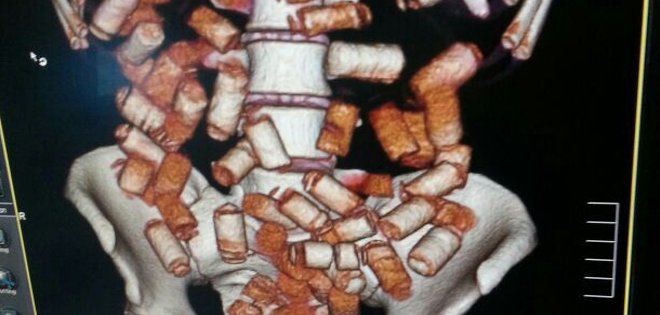

Una máquina de rayos X alerta sobre las sustancias ingeridas. Esta información la confirman a través de tomografías. Foto: Policía Antinarcóticos.

Una máquina de rayos X alerta sobre las sustancias ingeridas. Esta información la confirman a través de tomografías. Foto: Policía Antinarcóticos. -

Wilson Ibujés, jefe de la Unidad de perfiles del aeropuerto de Guayaquil, explica que una máquina de rayos X los alerta sobre las sustancias ingeridas. Esta información la confirman a través de tomografías, practicadas en el hospital de la policía, como algunas muestras de un hombre y una mujer en cuyos estómagos se almacenaba cápsulas de cocaína y preservativos con cocaína líquida.